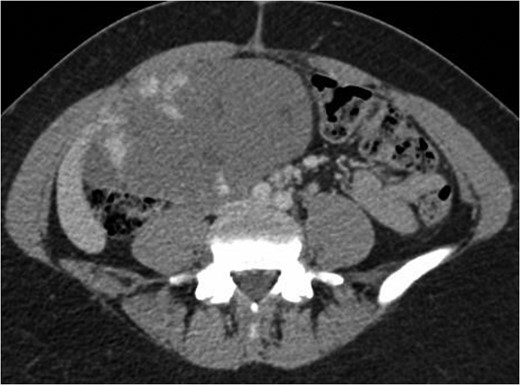

Axial CT image in portal venou phase at level slightly inferior to aortic bifurcation demonstrating the peripheral nodular enhancement of the haemangioma.